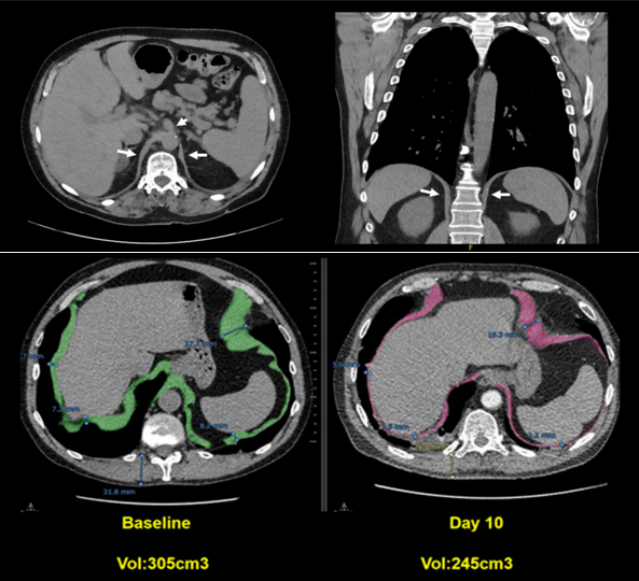

膈肌功能评估主要包括无创评估和有创评估。无创评估方法包括胸部影像学(胸部X线摄影、胸部CT、MRI)、肺功能、膈肌超声,有创评估方法包括压力测定(食道测压—跨膈压)、颤搐性跨膈压、膈肌肌电图。(1)胸部X线摄影:普通胸部X线摄影包括胸片与透视。胸片为静态检测手段,常用于单侧膈肌异常的诊断,如因肌纤维薄弱扩张所致的膈膨升、胸腹腔疾患所致的压力梯度异常或膈神经麻痹等。透视可动态评估膈肌的运动功能,是对胸片的进一步补充,并以观测膈肌运动幅度为主,但由于辐射及患者配合等问题在临床中并未广泛应用。图1为冠状动脉搭桥患者手术前后的胸片,术前胸片可见膈肌正常。术后2周患者出现呼吸困难,胸片可见左侧膈肌明显抬高,可能是由于术中损伤膈神经导致膈肌麻痹所致。(2)胸部CT:作为静态检测手段,胸部CT可以进行横断面扫描及三维重建,用于检测膈肌的器质性占位,三维重建能还原膈肌各部的立体结构,在残气量(RV)、功能残气量(FRC)、肺总量(TLC)等时相测量患者矢状位和冠状位的膈肌长度、表面积、膈穹隆、对合面积等,以此来量化膈肌的功能。图2所示为通过测量患者起病后第10天的膈肌宽度来估算膈肌的面积,结果发现膈肌面积缩小,提示存在膈肌萎缩及膈肌功能障碍。(3)胸部MRI/动态MRI:通过胸部MRI/动态MRI可以动态评估膈肌功能。如图3所示为正常人在TLC、FRC、RV三个体位时的膈肌形态,可以发现,从FRC到TLC时,膈肌明显下移。图4所示为对肌萎缩侧索硬化(ALS)患者膈肌进行的动态监测,在正常人在吸气和呼吸时,膈肌有明显的位移。但是ALS患者出现呼吸衰竭,无论是吸气还是呼气,膈肌位移都非常不明显,提示患者可能存在膈肌麻痹。